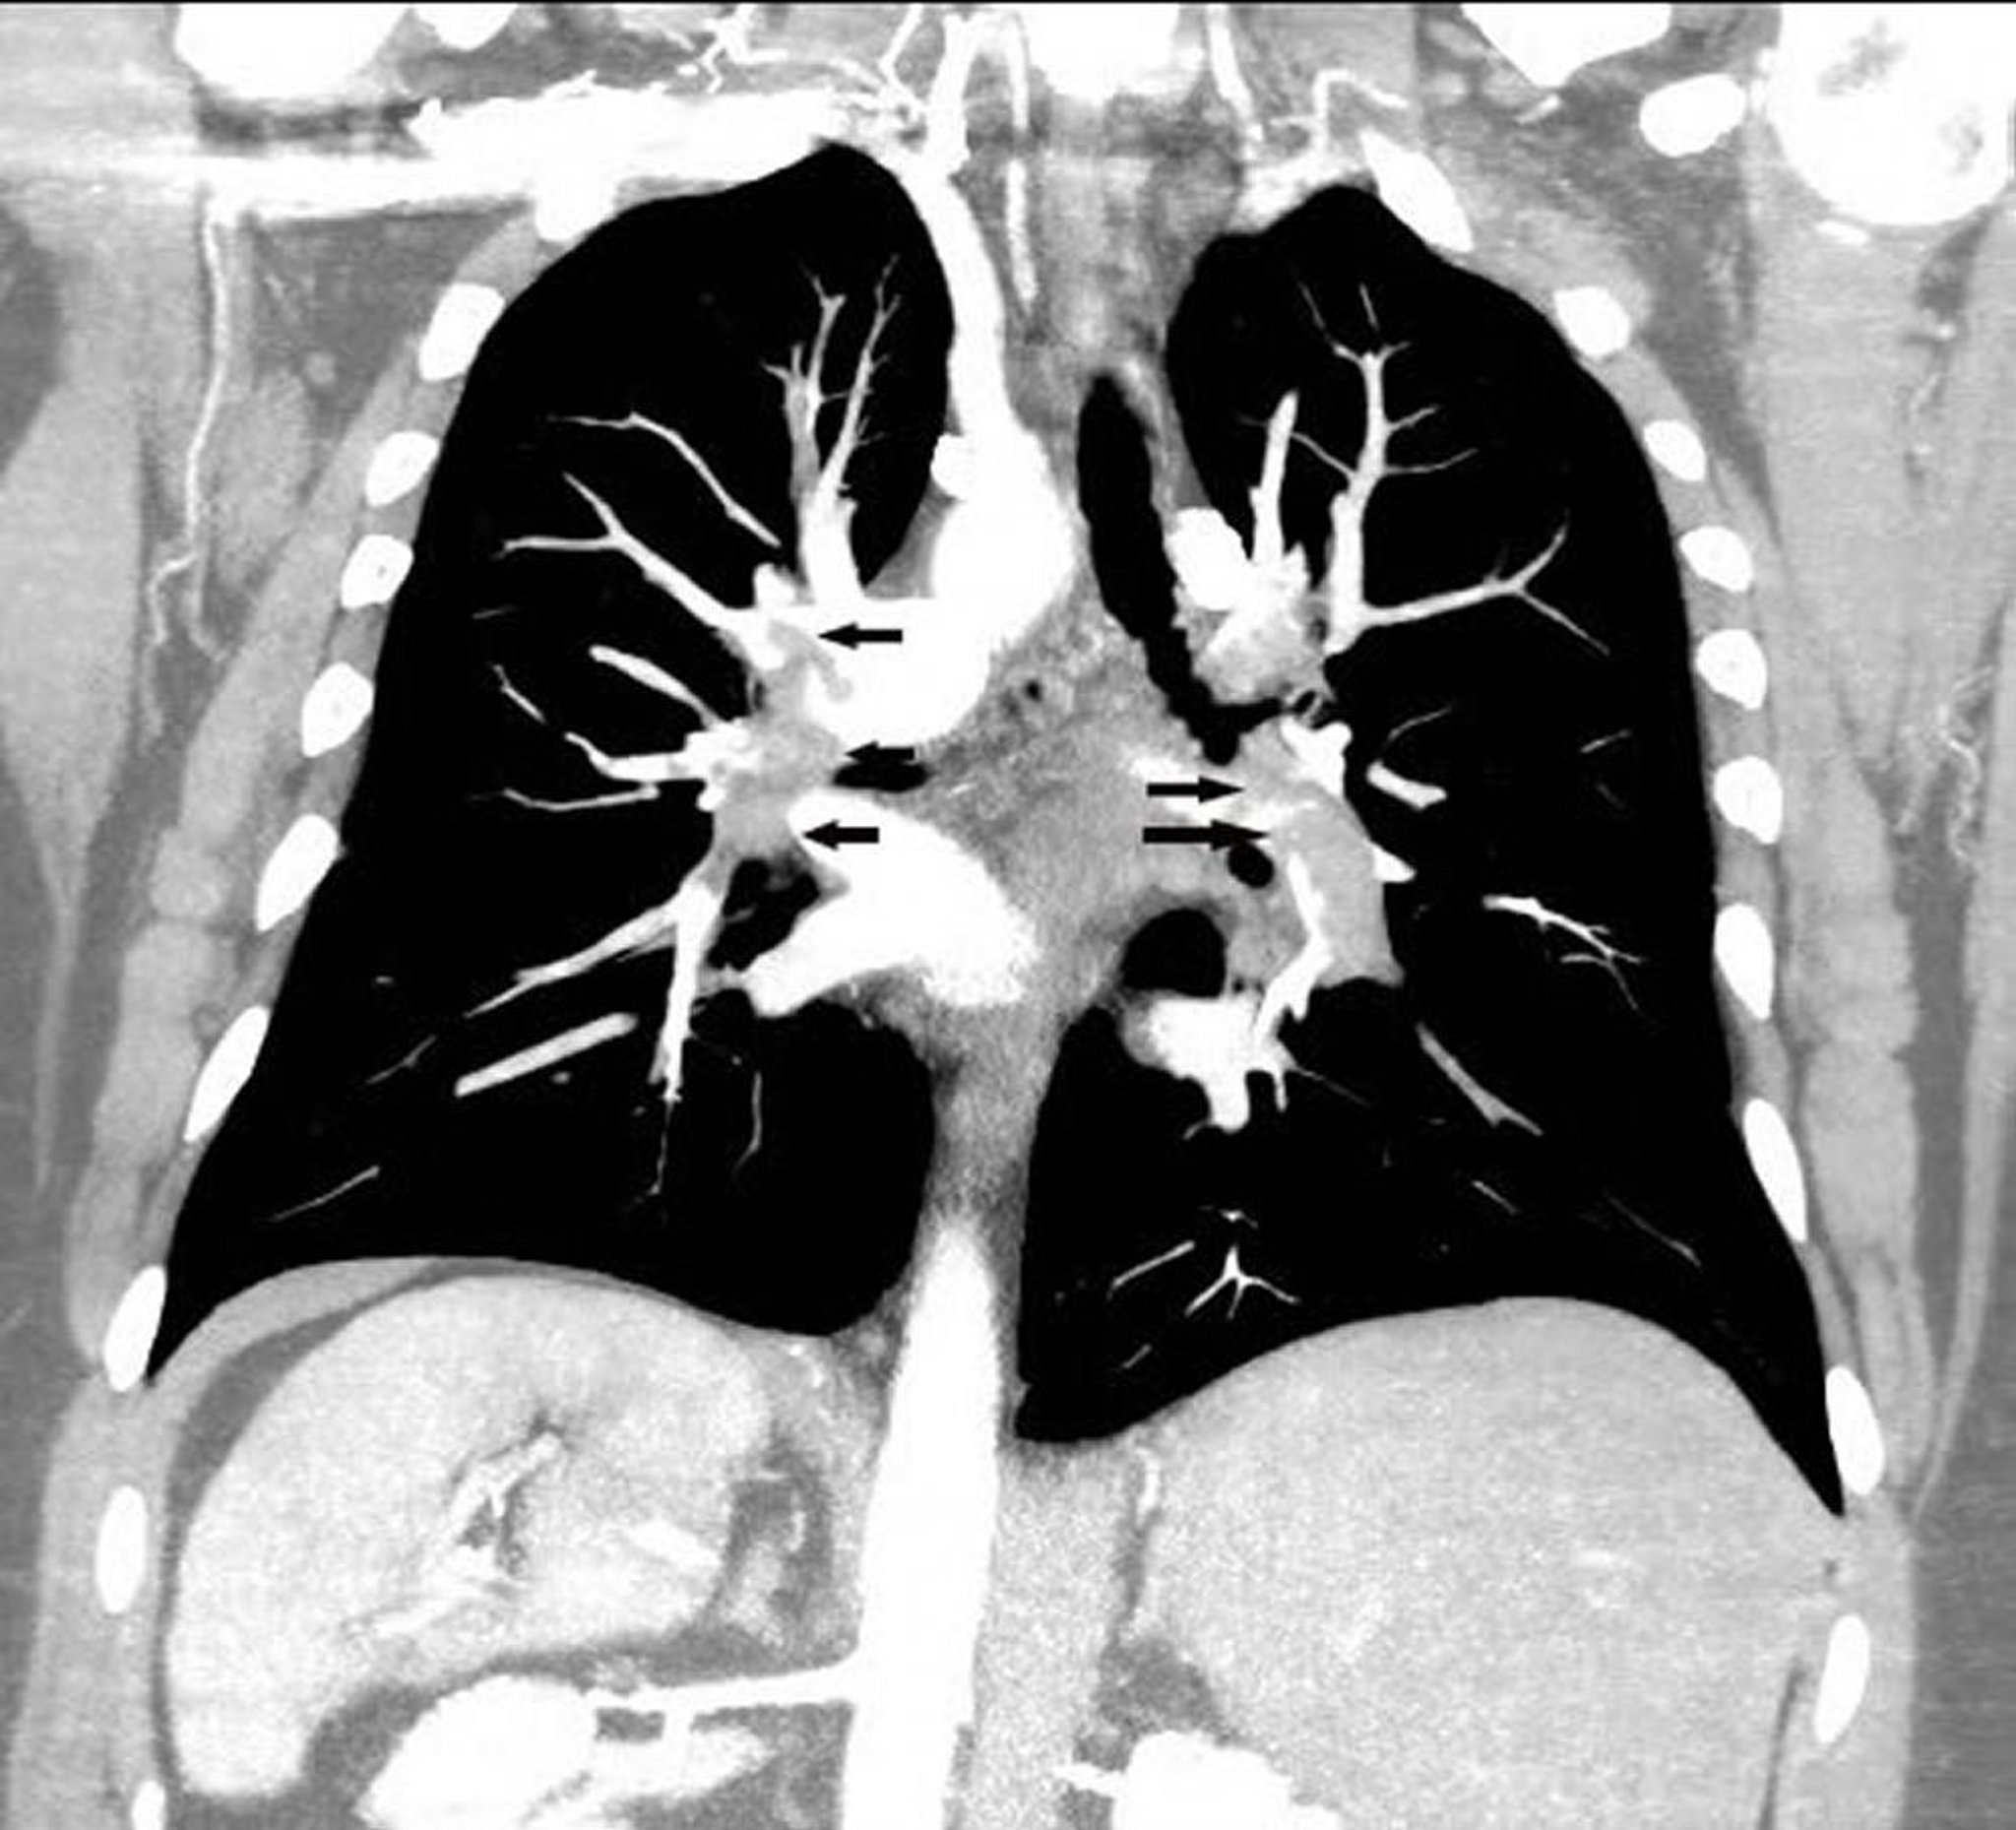

Coronal reconstruction CT pulmonary angiogram shows an extensive pulmonary embolus in both pulmonary arteries (arrows).

Image courtesy of Hakan Ilaslan, MD.